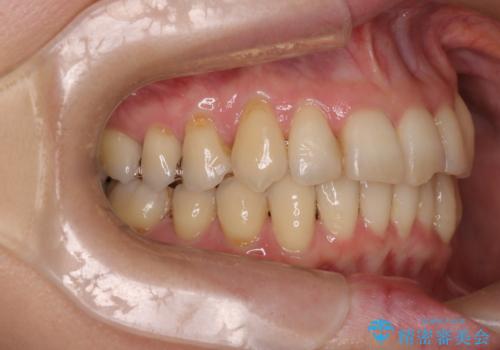

- 上下の歯の凸凹を主訴に来院されました。

他院では抜歯+ワイヤー矯正の提案をされているとのことでした。

当院での検査にて非抜歯+インビザライン矯正を提案させていただき治療を行なっております。

患者様にしっかりとインビザラインを使用して頂けたことで綺麗な仕上がりとなりました。